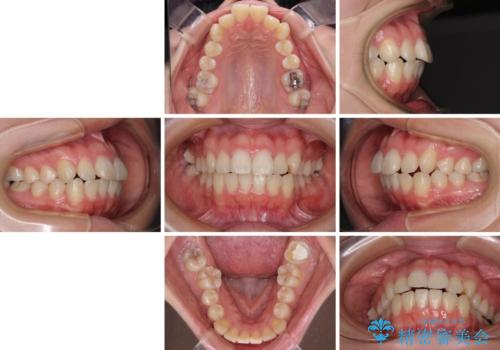

- 口元の突出感を気にして来院された患者様です。

口元を積極的に引っ込めるために、上下左右の第一小臼歯を4本抜歯することとし、ワイヤー装置による矯正治療を行うこととしました。

上下前歯がくちばしのように突出していましたが、抜歯矯正により口元が引っ込み、唇が閉じやすくなり、鼻の下の膨れた感じも解消されました。